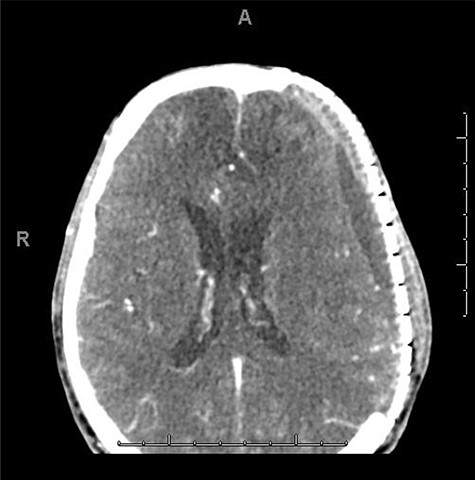

He had a significant recovery, to the point where he was awake with mild right paresis. He was following commands briskly but remained nonverbal. On hospital day 26, he developed neurological deterioration with decreased mental status and worsening right hemiparesis. Clinical examination noted pronounced new indentation of his hemicraniectomy flap site. CT head showed a rightward shift away from the craniectomy site and impending herniation (Fig. 4).

CT head POD26 from craniectomy demonstrating findings consistent with SSFS.